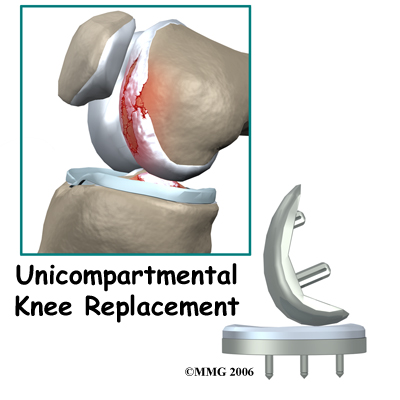

Unicompartmental Knee Replacement

A painful knee can severely affect your ability to lead a full, active life. Over the last 25 years, major advancements in artificial knee replacement have improved the outcome of the surgery greatly. One of the more recent advances in knee replacement surgery is the unicompartmental knee replacement (also known as a unicondylar knee replacement). This type of knee replacement is less invasive than a full knee replacement. The operation is designed to replace only the portions of the joint...